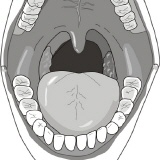

Inspektion der Mundhöhle - klinische Untersuchung

Es folgt die so genannte klinische Befundaufnahme - mit einfachen Worten die Erfassung der momentanen Mundsituation.

- Zahn und Lückensituation

- Kariöse Zähne

- Defekte Füllungen

- Zustand des Zahnhalteapparates (liegt eine unbehandelte Parodontose vor)

- Entzündungen in der Mundhöhle

- Kieferrelation (Zuordnung des Oberkiefers zum Unterkiefer)